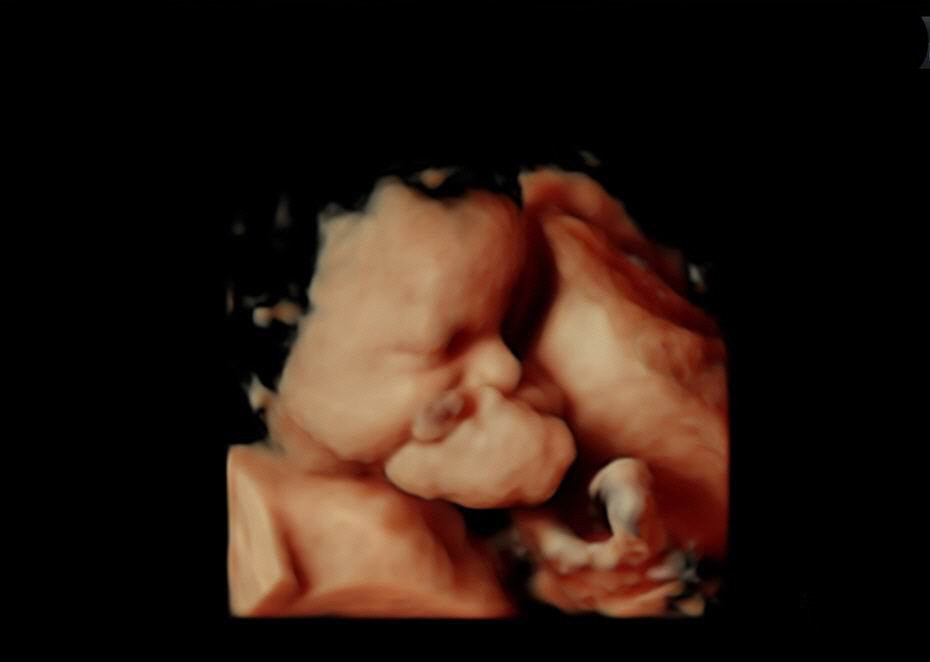

Primera intervención EXIT realizada en la Región de Murcia a un feto de 30 semanas (ecografía feto)